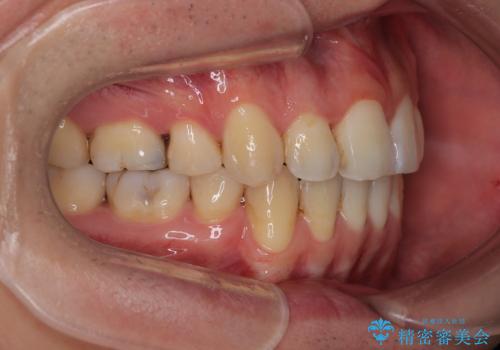

口元の突出が改善され、横顔の印象が大きく変化し、口が自然に閉じやすくなりました

前歯のデコボコが整い、清掃性が向上

噛み合わせが改善し、長期的に安定する噛み合わせに

「見た目」と「機能性」の両方を改善できた、非常に満足度の高い治療となりました。